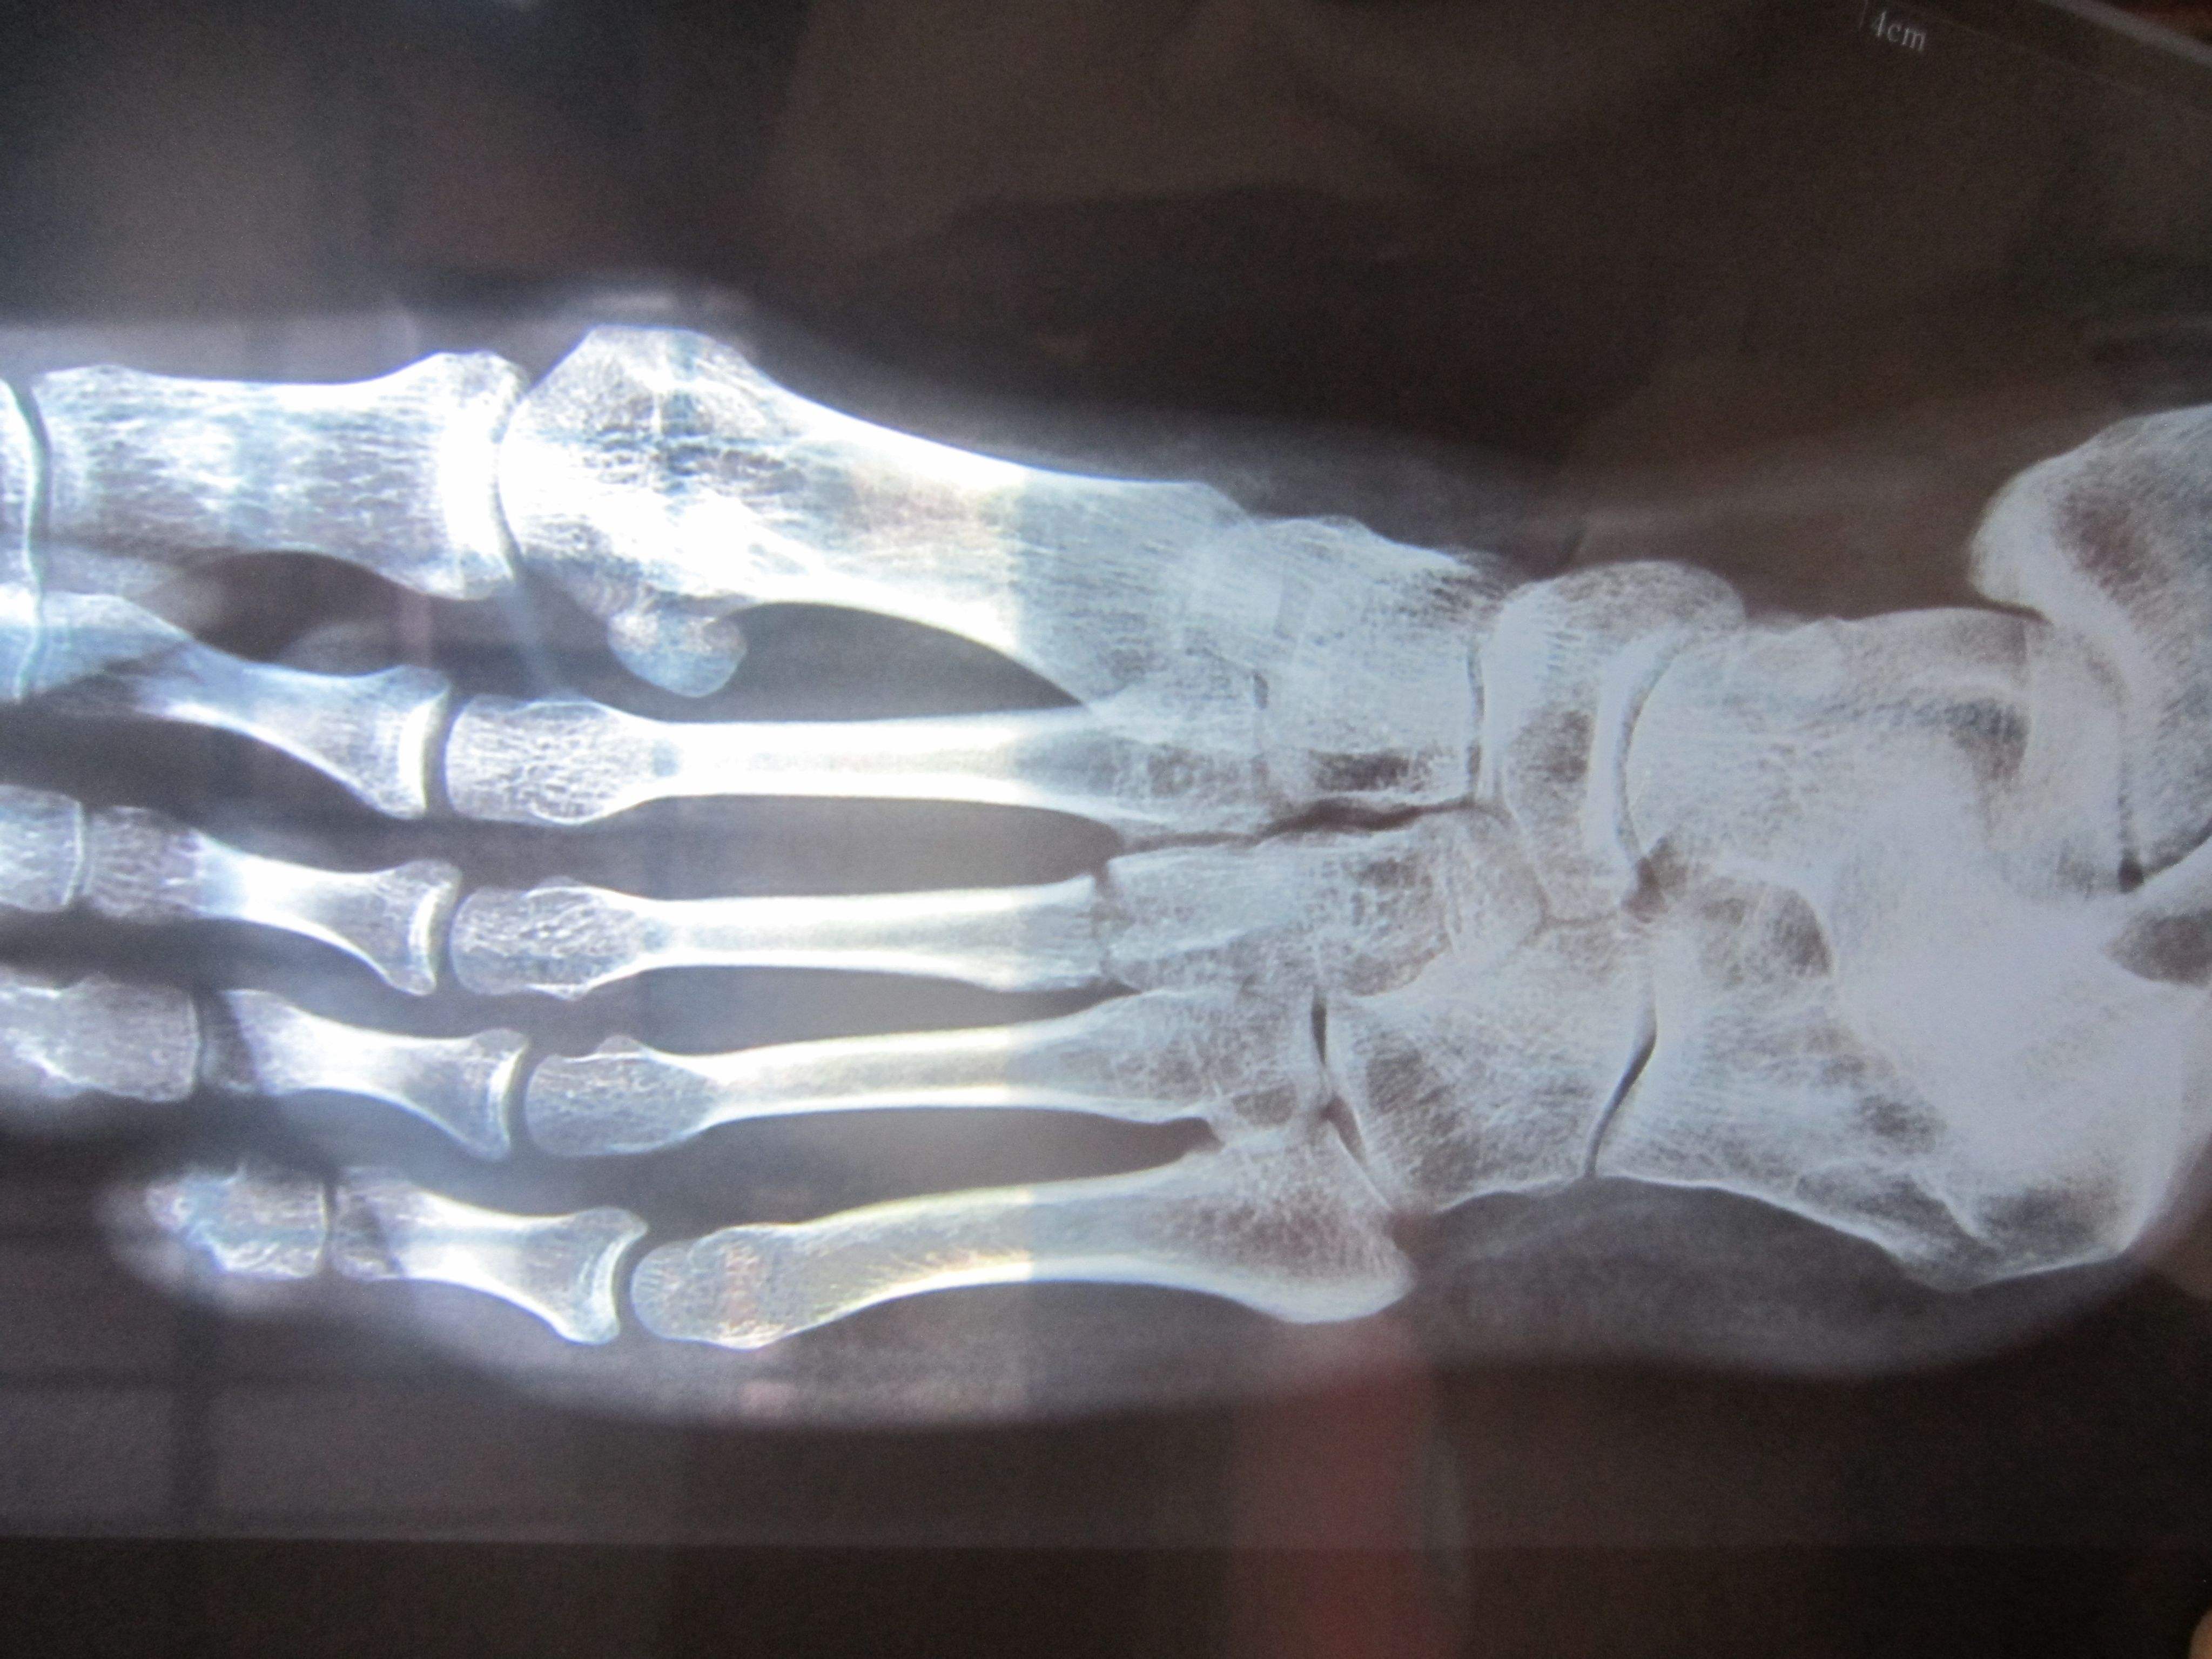

跖骨骨折多因重物打擊足背、輾壓及足內翻扭傷引起。跖骨干骨折因相鄰跖骨的支持,一般移位不大。第2、3跖骨頸部易發生應力骨折(疲勞骨折)。第5跖骨基部骨折是由于足突然內翻,腓骨短肌猛烈收縮撕脫造成,很少移位,需與該部未閉合的骨骺相鑒別。